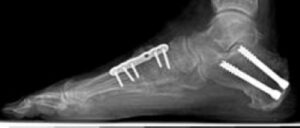

Osteotomies involve cutting and repositioning bones to restore a more natural arch shape, reducing strain on the posterior tibial tendon and supporting ligaments. Common procedures include moving the heel bone (calcaneus) to its proper position and lengthening the outer portion of the heel to correct the "too many toes" deformity. Bone grafts and fixation devices like screws or plates may be used to ensure proper healing.

X-ray of a foot as viewed from the side in a patient with a more severe deformity. This patient required fusion of the middle of the foot in addition to a tendon transfer and cut in the heel bone.